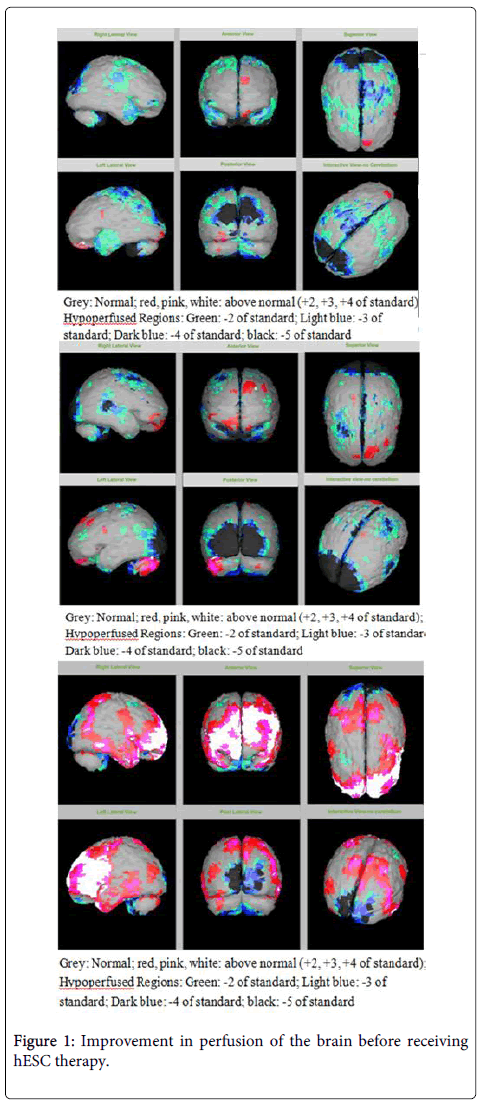

該患者的SPECT掃描如圖1和2所示。

圖1:接受hESC治療前大腦灌注的改善。

SPECT掃描

在研究開始和結束時,23名患者接受了SPECT掃描。在枕葉或額葉或雙葉中觀察到灌注不足。23例接受SPECT掃描的患者中,5例患者表現為枕葉灌注不足,7例患者表現為額葉灌注不足,11例患者表現為枕葉和額葉灌注不足。

總體而言,治療結束時,2名患者的灌注正常,18名患者(12名男性和6名女性患者)顯示灌注顯著改善(>60%),3名患者顯示灌注中度改善(30-60%)。大多數在接受hESC治療前額葉和枕葉嚴重低灌注的患者在接受 hESC 治療后情況有所改善。23名可獲得SPECT掃描報告的患者的GMFCS評分在hESC治療后有所改善(表2)。

眾所周知,神經干細胞可以通過重新填充受損區域并防止細胞進一步退化來恢復正常視力。hESC通過增殖成相似的細胞類型來啟動受損細胞的再生。在本研究中觀察到灌注改善,這反映在SPECT掃描中。詹森等人研究顯示,一名5歲腦癱患者在接受臍帶血干細胞治療2個月后視力有所改善。